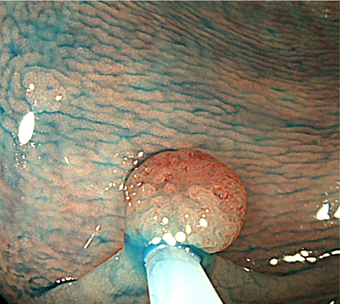

3)内視鏡的粘膜下層剥離術(ESD)

2cmを越える大きな腫瘍では、通常の内視鏡的ポリープ切除や粘膜切除術では一度に切除することが難しくなります。何度かに分割して切除すると再発率が高いため、内視鏡的粘膜下層剥離術(ESD)で腫瘍全体を一度に切除する方法を行います。ESDではヒアルロン酸溶液などを粘膜下に注入し病変を盛り上げてから、ナイフで少しずつ病変を削り取って切除します。現在のところ大腸がんに対するESD は高度先進医療実施施設でのみ実施が可能です。大きな潰瘍ができるため出血や穿孔の危険性が高くなるため、通常1週間くらいの入院が必要です。